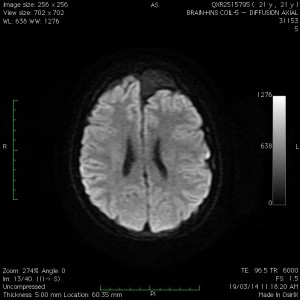

The most common location is the middle fossa (“Sylvian” or fronto-temporal), followed by the cerebellopontine angle and other regions of the hindbrain, and then other miscellaneous sites such as the cerebral convexity (like the one shown above) and the sellar region (around the pituitary gland). Initial imaging is usually a CT scan, followed by an MRI. The classic feautures are demonstrated in the MRI above. Dr Khurana recommends at least two MRI studies separated by at least 6 months, and one of the MRI studies to be with contrast, for proper characterisation and surveillance of the cyst.